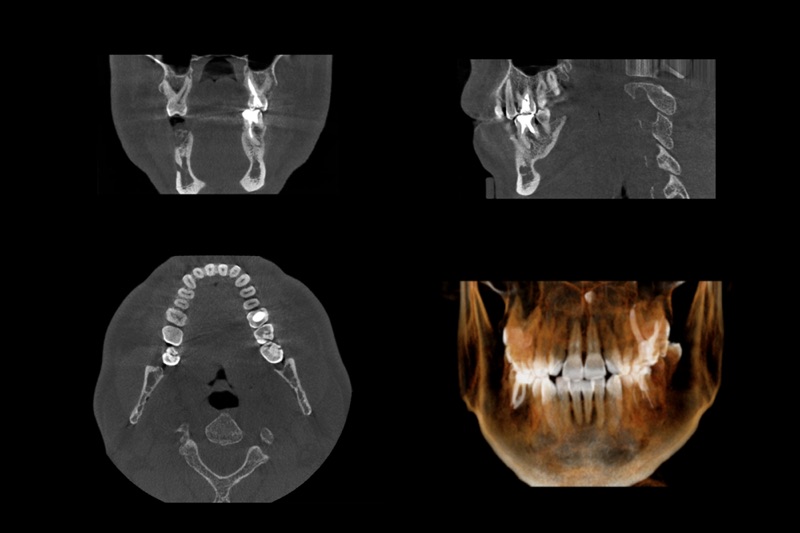

歯科用CTを使った正確な診断

歯周病は進行すると骨が溶けてしまう病気ですが、 2次元パノラマの歯科用レントゲンでは骨の厚みや密度まで確認することはできません。

当院で導入している歯科用CTは3次元画像で診断が出来るため、歯や顎の骨の状況を立体的に把握でき、歯周病の進行度を正確に診断することができます。